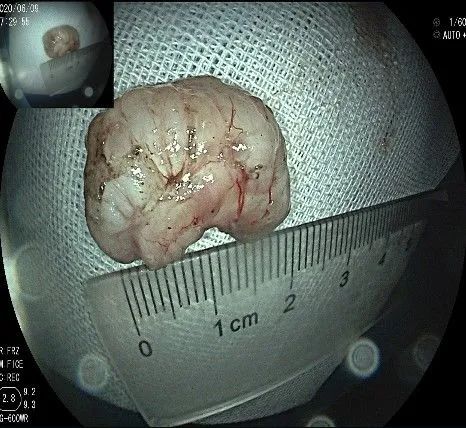

瘤子完整切除,随透明帽吸出的时候脱落到左侧会厌部,当时我们团队的麻醉、护理等人员都捏了一把汗,因为是静脉全麻没有插管,离声门太近了,一不小心进入气道会形成气管异物,造成严重后果!迅速换用鳄齿钳钳夹牢固,顺利取出!

完整的瘤体,呈不规则形状,长约2.0cm,宽度约0.8cm,有一定厚度,触之韧,像一颗白色的肾,表面有血管网。尽快浸泡送检。